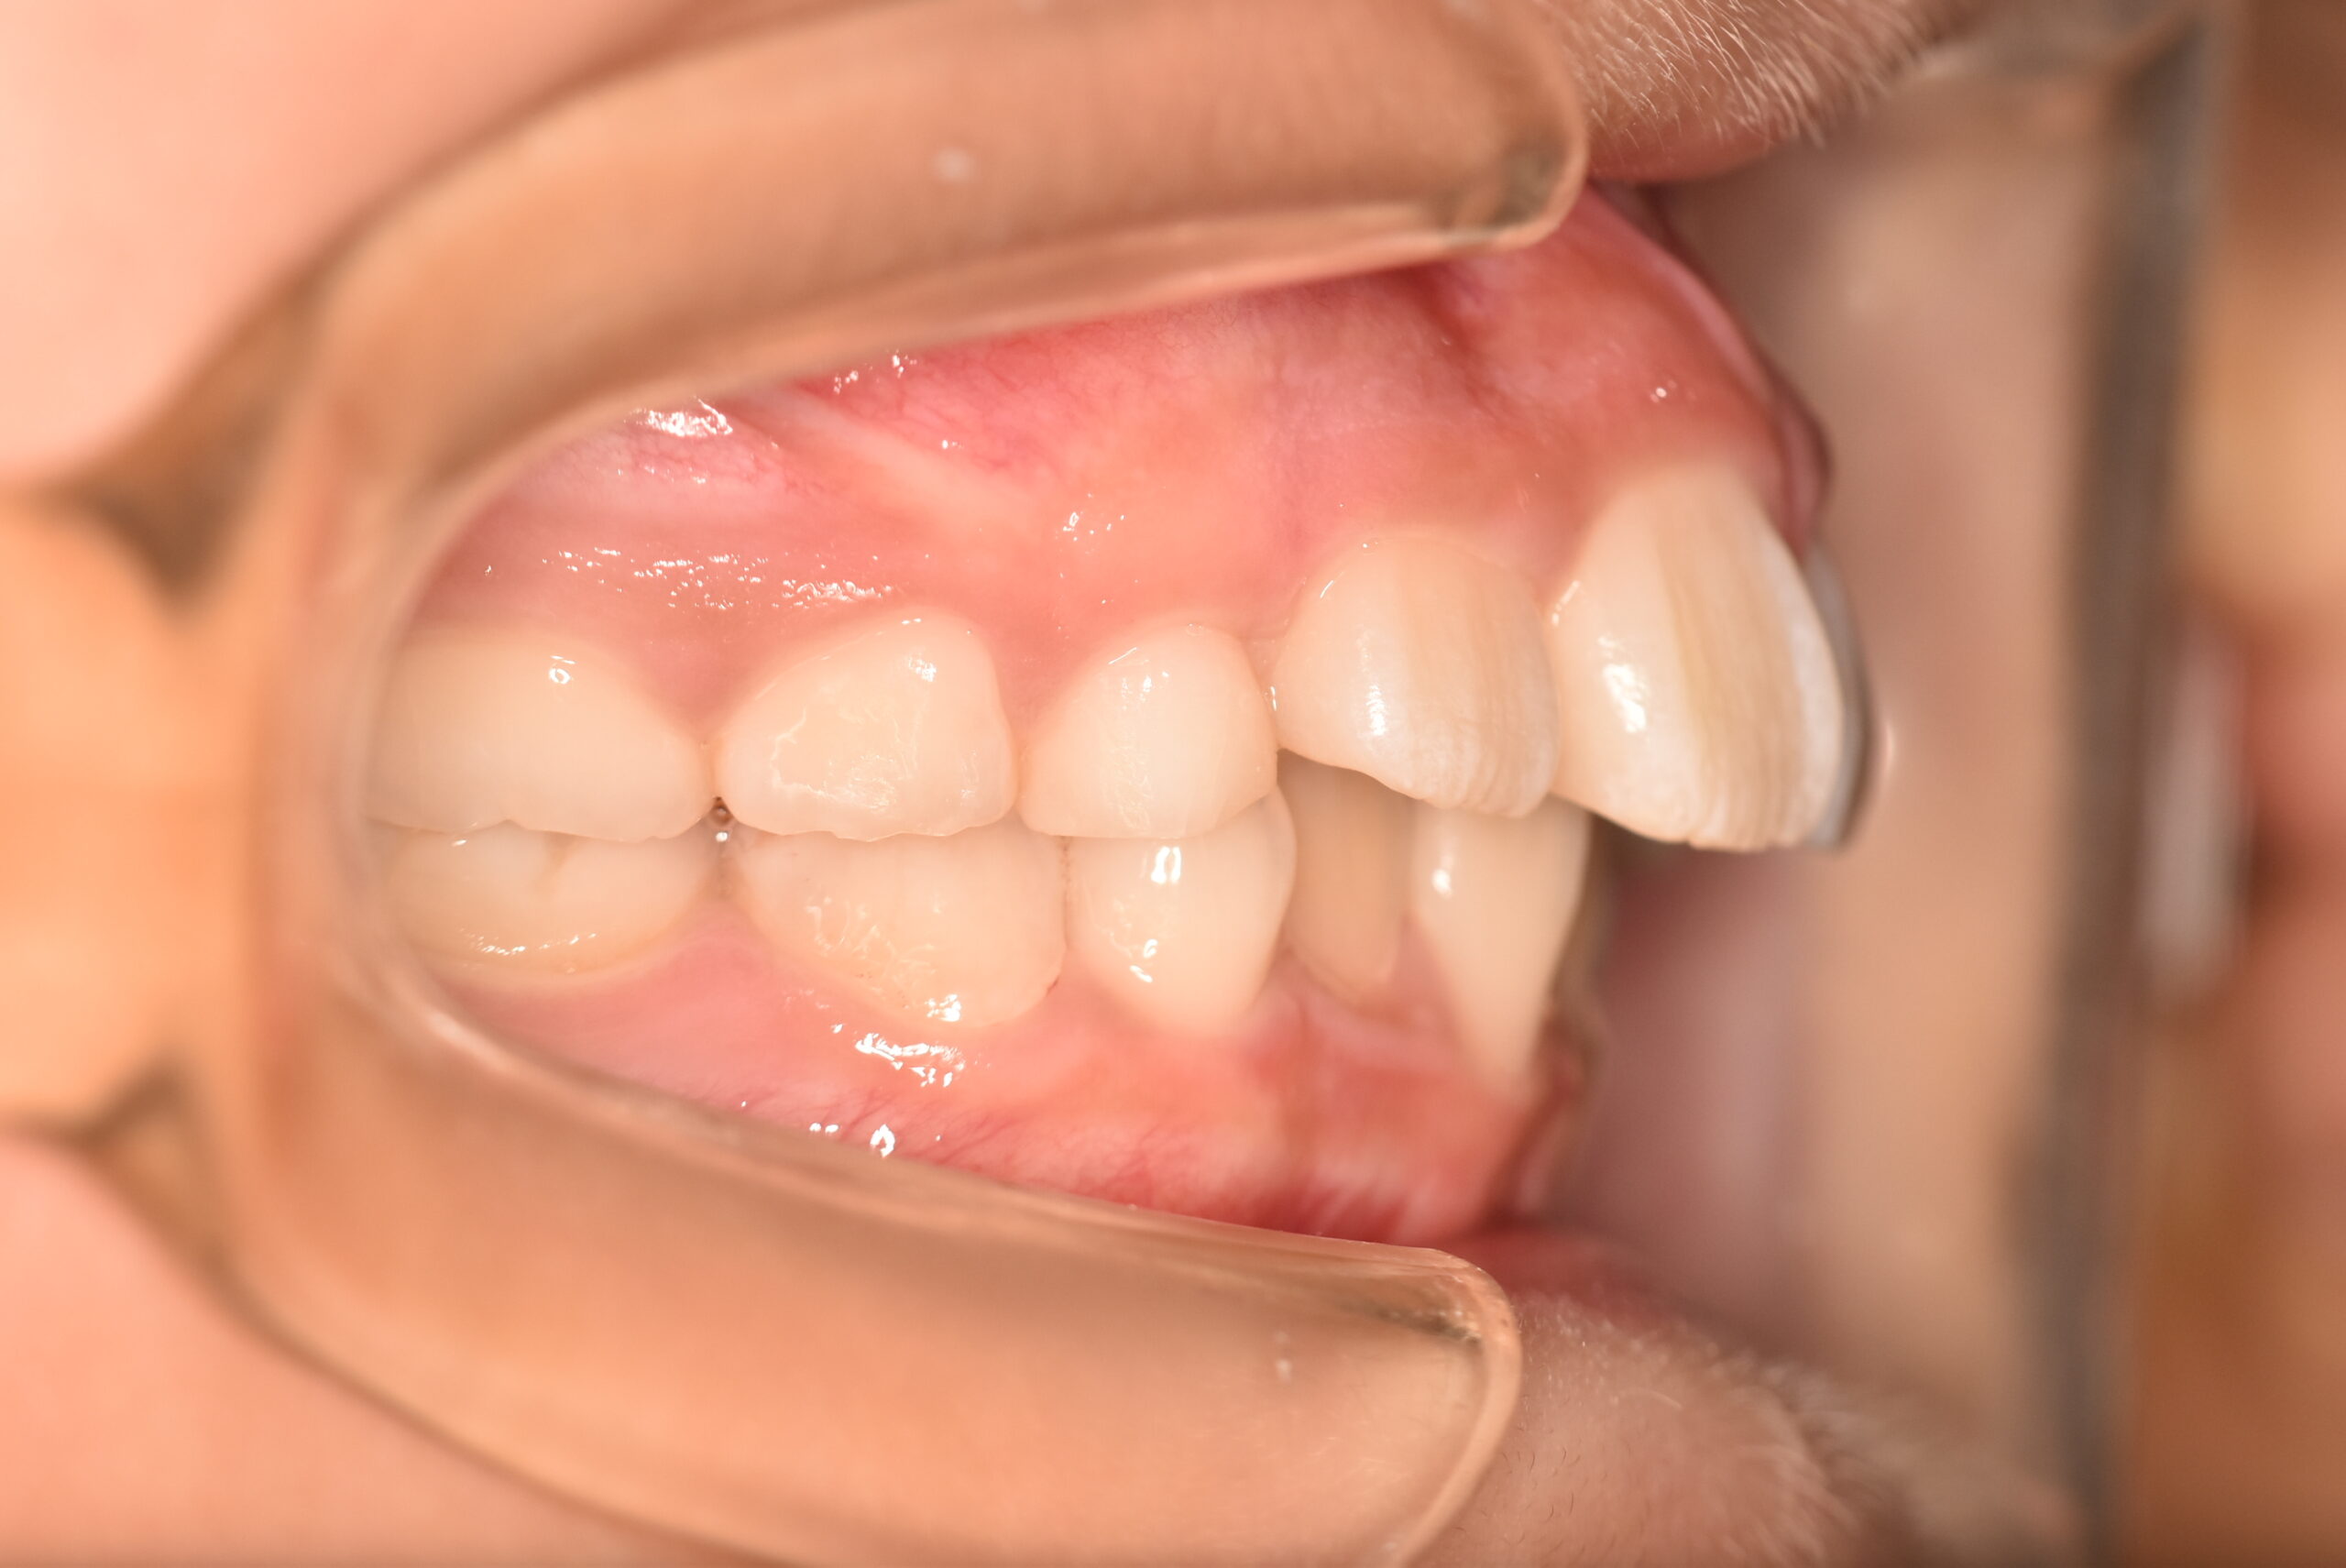

| 治療内容の詳細 | 初診時7歳の女児で、歯のがたつきを気にされ来院されました。 検査の結果、前歯部叢生を伴うアングルⅡ級不正咬合と診断しました。 治療としてはマウスピース矯正(インビザラインファースト)で配列を行い、上下顎の側方拡大と萌出スペースを確保しました。 治療期間は、1年でした。 今後、側方歯生え変わりまで経過観察を行います。 |